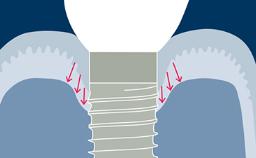

O sucesso do tratamento com implantes requer um plano com orientação protética para determinar a posição ideal do implante. A posição do implante deve facilitar a instalação de uma prótese definitiva ideal que atenda às exigências funcionais e estéticas e mimetize a dentição natural.

Usando investigações diagnósticas adicionais, os requisitos cirúrgicos e protéticos específicos da região podem ser identificados e avaliados. Isso ajuda a minimizar o risco de complicações e falhas após o tratamento com implantes.